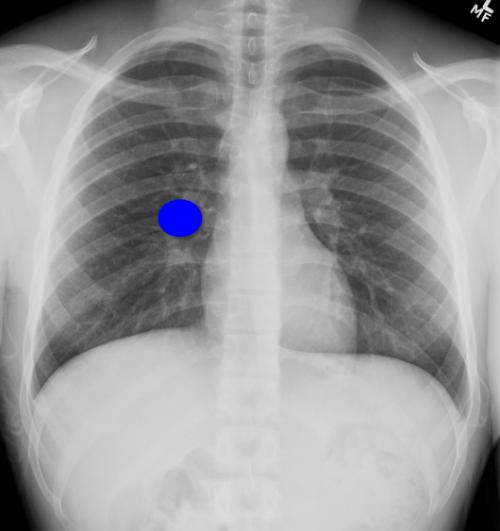

In which anatomical areas could the simulated mass potentially be localized on this PA?

Choose all that apply

Anterior chest wall

Anterior pleura

Right lung

Right hilum

Mediastinum

Posterior pleura

Posterior chest wall